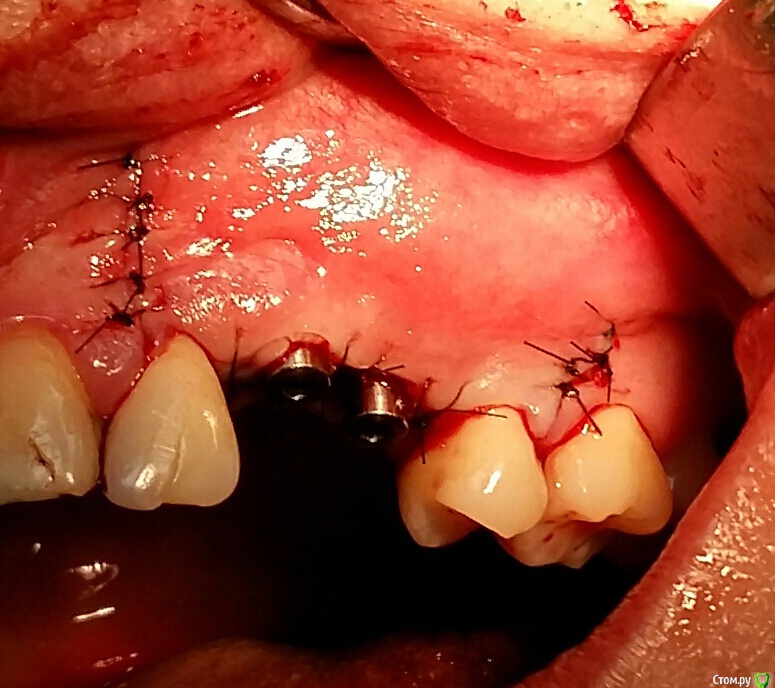

Kostoprav Опубликовано 26 марта, 2017 Поделиться Опубликовано 26 марта, 2017 (изменено) извините за качество фотографт: ауто + биопласт крошка, мембрана еволюшендырка возле 22-ревизия периапикального процесса Изменено 26 марта, 2017 пользователем Kostoprav 3 Ссылка на комментарий

Dman Опубликовано 27 марта, 2017 Поделиться Опубликовано 27 марта, 2017 Почему приняли решение ушивать с формирователями а не наглухо? Ссылка на комментарий

Kostoprav Опубликовано 27 марта, 2017 Автор Поделиться Опубликовано 27 марта, 2017 Почему приняли решение ушивать с формирователями а не наглухо?использовал фдм что бы не пиниться с небной стороны Ссылка на комментарий